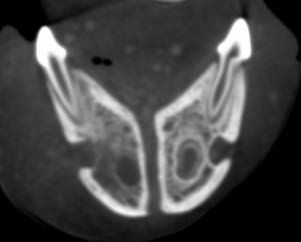

A six-month-old mix breed canine patient weighing 61 lbs (27.9 kg) presented for swelling associated with the eruption of the #405 adult tooth. The DVM performed an FNA that was unremarkable. Differential Dx includes dentigerous cyst, infection, or some kind of cancerous process. The DVM used his Vimago HDVI CT to perform a scan of the skull to gather more information.

Survey and post-i.v. contrast CT of the skull

Oral cavity: Poorly marginated soft tissue swelling with fat stranding in the region of the 405

Dentition: periodontal lysis is seen surrounding the root of 405. No missing teeth seen. Poorly marginated lysis of the mandible in the root region of 404 and 404.

Rostral right mandibular region selling and mandibular lysis: possible osteomyelitis; periapical infection, septic focus, lucent foreign body

Oral examination for lesions of teeth 404, 405